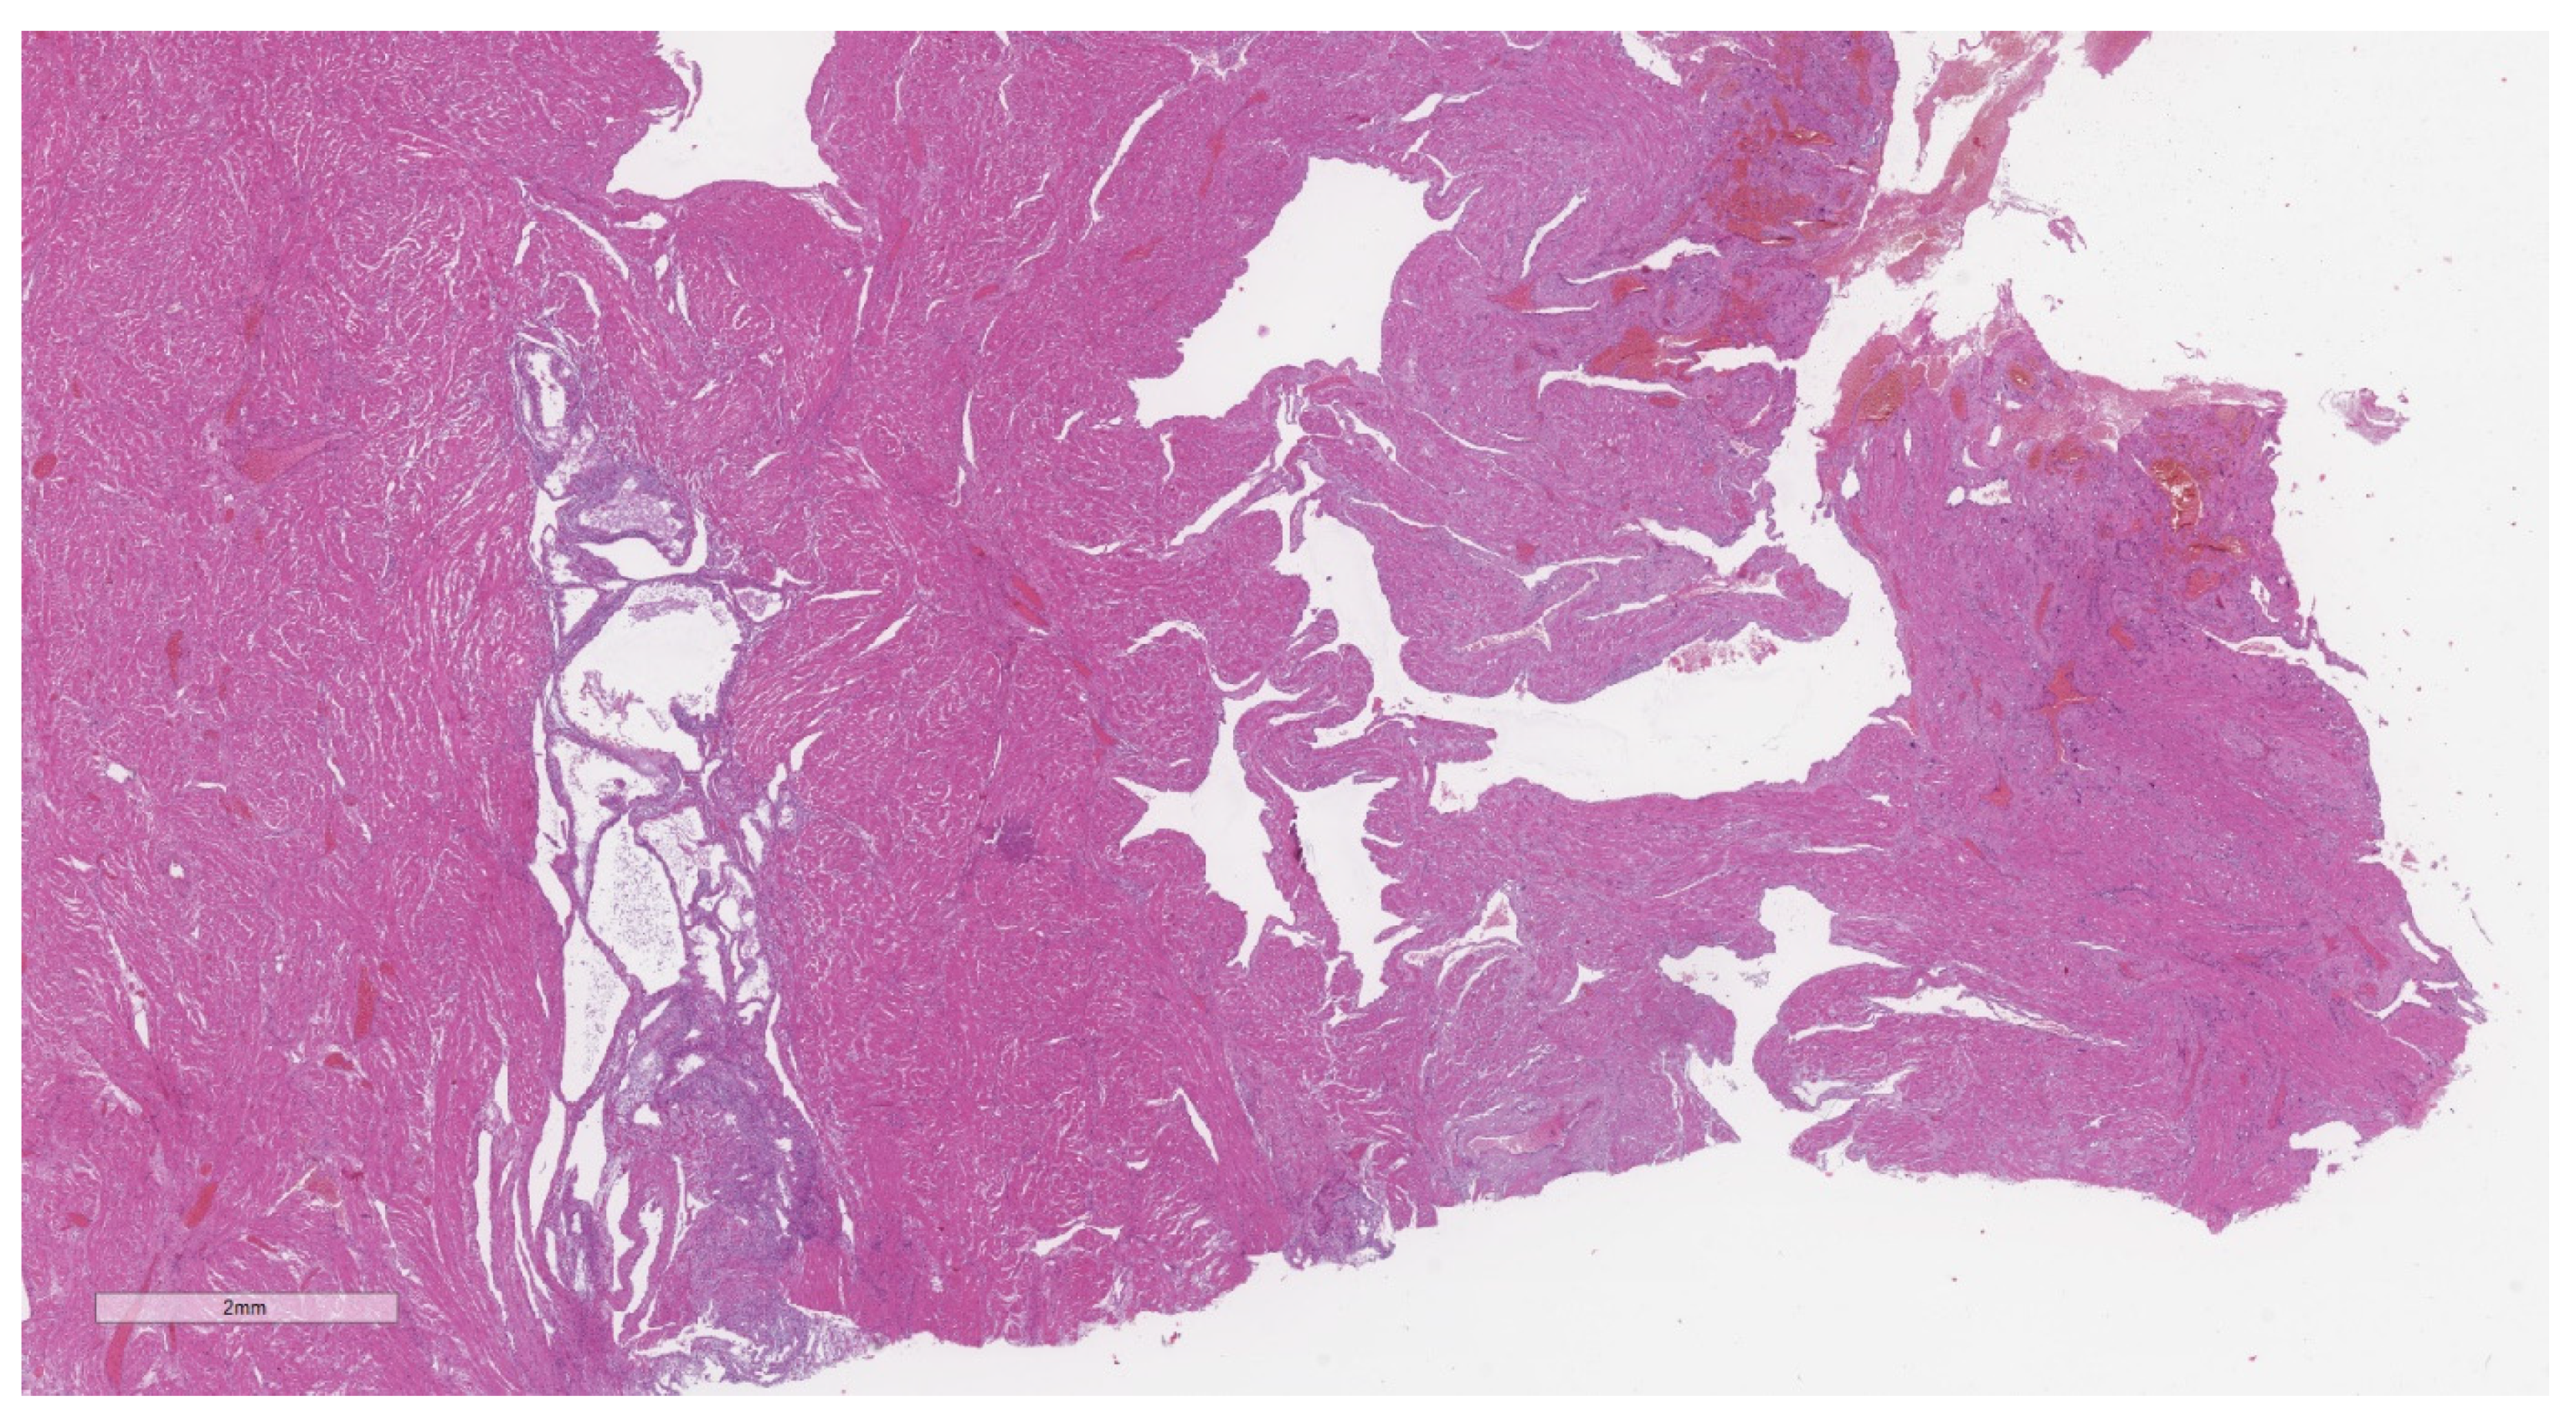

2.2. Histopathological Analysis